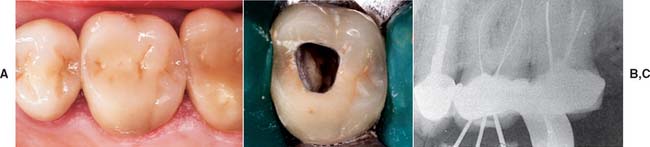

Dental caries (Fig. 32-8) is the most common cause of failure of a cast restoration.9-12 Detection can be very difficult,13 particularly where complete coverage is used. At each appointment, the teeth should be thoroughly dried and visually inspected (Fig. 32-9). The explorer must be used very carefully when early enamel lesions are assessed, because a heavy-handed examination may damage the fragile demineralized enamel matrix. An intact enamel matrix is essential for procedures that induce remineralization14 (e.g., improved plaque control, dietary changes, topical fluoride applications).

Fig. 32-8 Undetected caries beneath this partial fixed dental prosthesis resulted in serious complications.